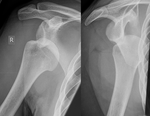

Hill–Sachs fracture Harold Arthur Hill

Maurice David Sachs

impacted posterior humeral head fracture occurring during anterior shoulder dislocation Hill Sachs Lesion Archived 2020-09-20 at the Wayback Machine at Wheeless' Textbook of Orthopaedics online Dislocated shoulder X-ray 03.png